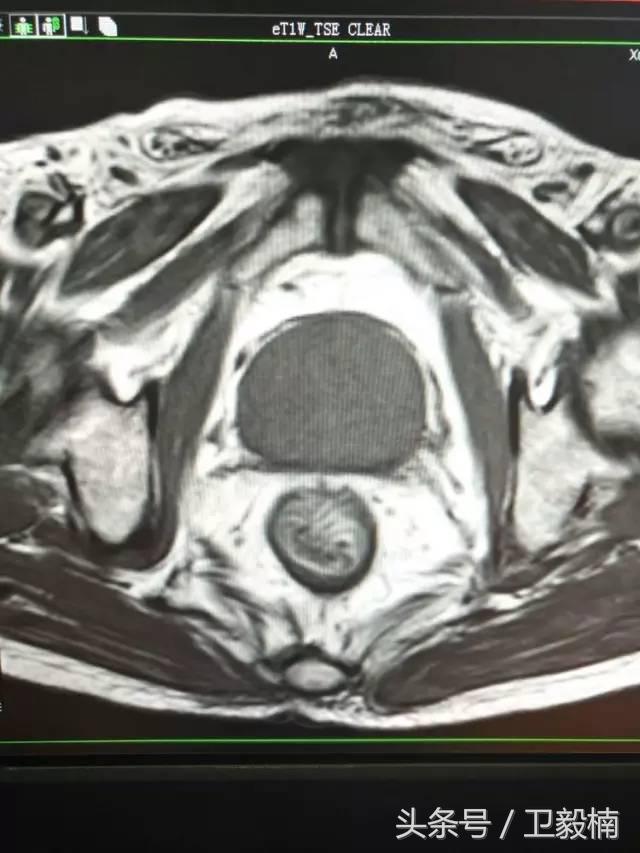

4. 在MRI引导下。